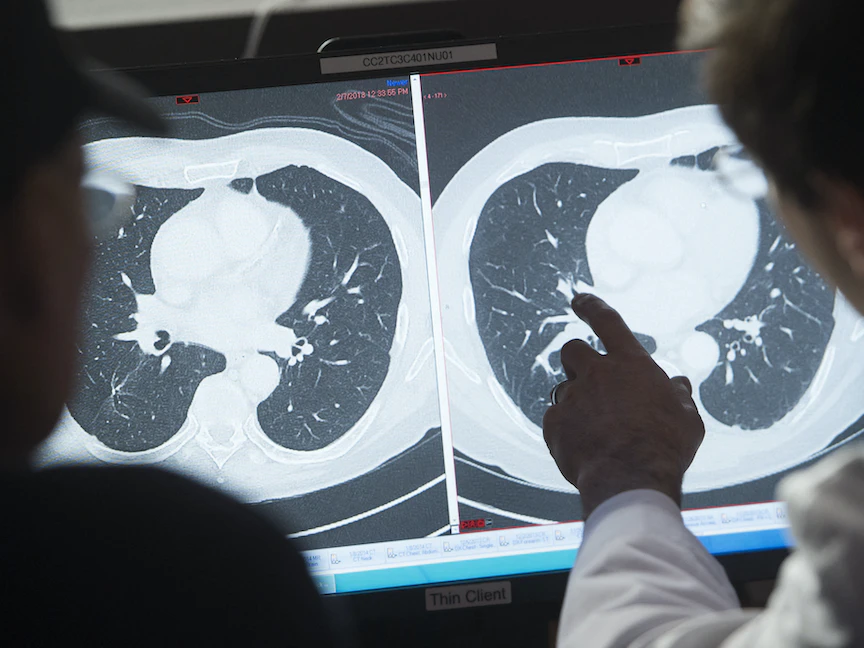

ومع ذلك، يمكن أن يتطور الورم الأرومي العصبي أيضاً في مناطق أخرى بالبطن وفي الصدر والرقبة وبالقرب من العمود الفقري، حيث توجد مجموعات من الخلايا العصبية.

- الوَرَم الأرومي العصبي في الصدر ربما يتسبب في ظهور علاماتٍ وأعراضٍ مثل: